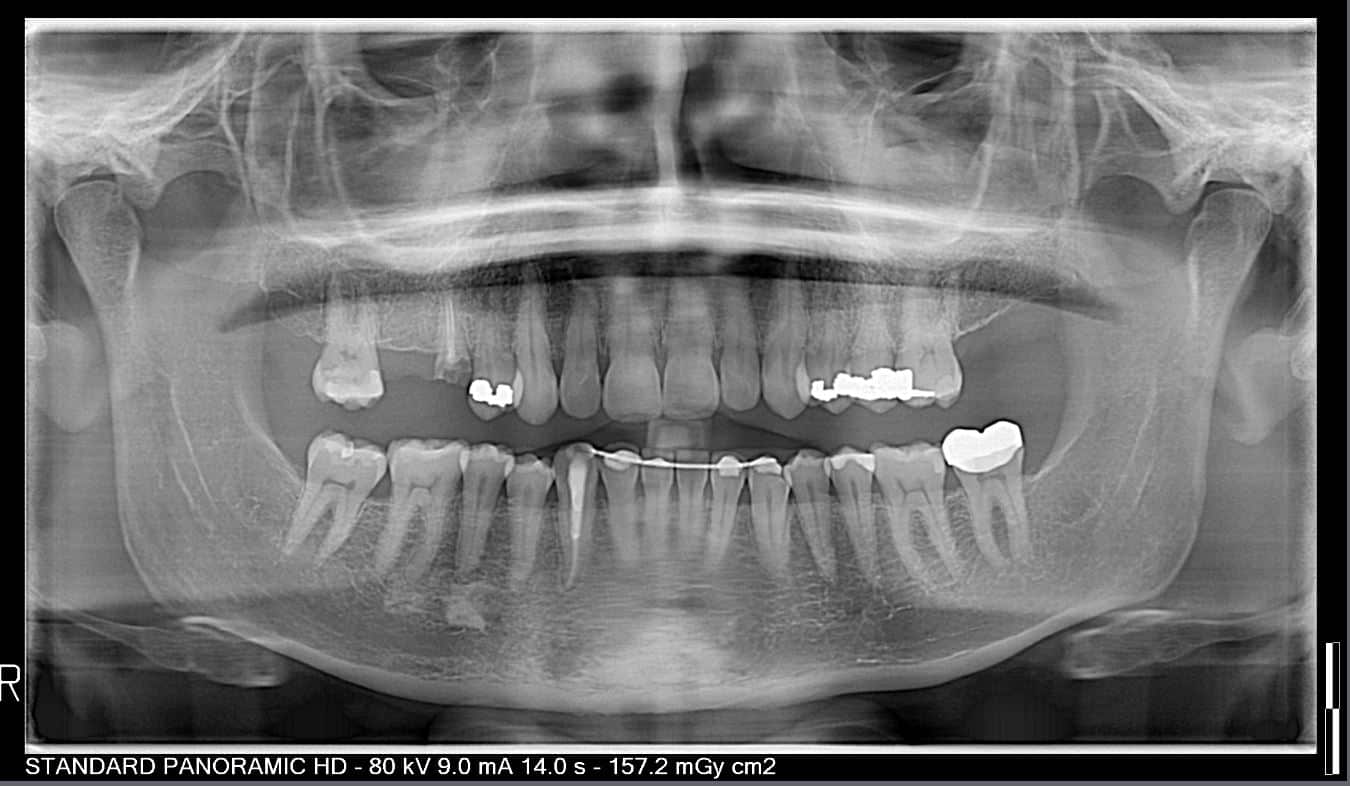

Before and After Image Gallery